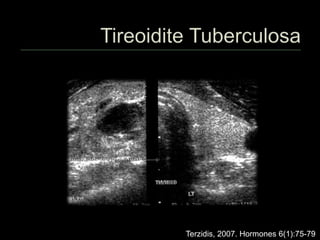

 Muito rara

 Formas de acometimento

 Miliar

 Focal

 Difusa

 Lesões caseosas

 Comum associação com acometimento

linfonodal pela Tb

 A forma focal pode simular nódulo maligno

 PAAF pode auxiliar no diagnóstico

Terzidis, 2007. Hormones 6(1):75-79